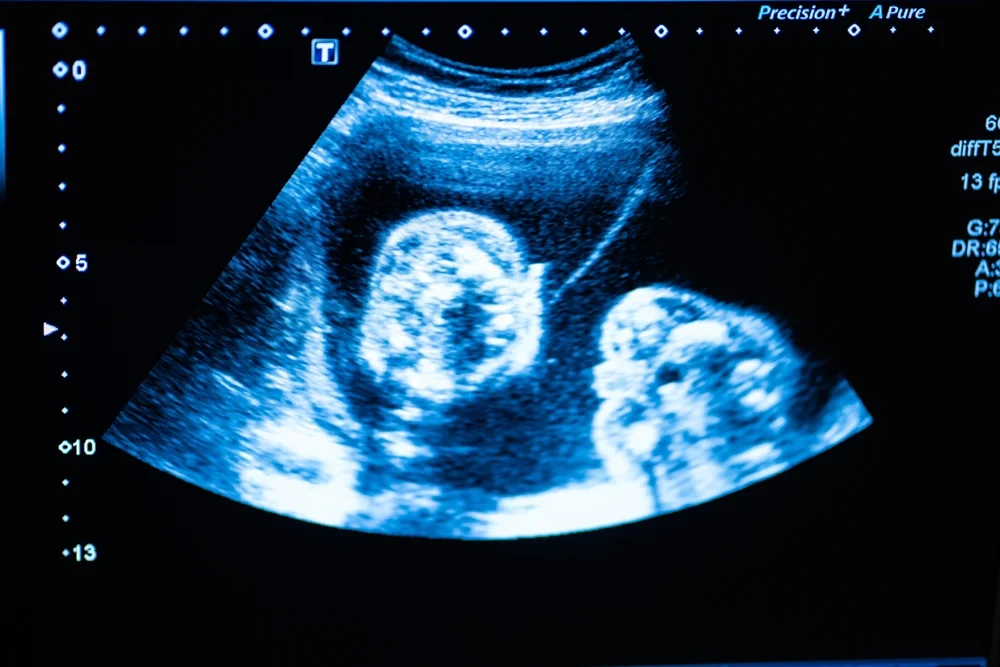

Gebeliğin ilk aşamalarında, döllenmiş yumurta rahim duvarına tutunur. Normal bir süreçte bu yumurtanın hem bir plasenta (bebeğin eşi) hem de bir embriyo oluşturması beklenir. Ancak boş gebelik durumunda, gebelik kesesi oluşmasına ve plasenta gelişmeye devam etmesine rağmen, kese içerisinde bebek (embriyo) gelişmez.

Vücut, hamilelik hormonu olan hCG salgılamaya devam ettiği için kişi kendini hamile hisseder, testler pozitif çıkar. Ancak ultrason muayenesinde boş bir kese ile karşılaşılır.

Boş gebelik tanısı sadece ultrasonda konulabilir. Genellikle gebeliğin 6. ila 8. haftaları arasında yapılan kontrollerde uzman doktor, gebelik kesesinin belirli bir milimetreye (genellikle 25 mm) ulaştığı halde içinde embriyo veya yol kesesi olup olmadığına bakar. Eğer kese boşsa ve transvajinal ultrasonla teyit edilmişse tanı kesinleşir. Doktorlar genellikle yanlış teşhis riskini önlemek için birkaç gün bekleyerek tekrar kontrol yapar.